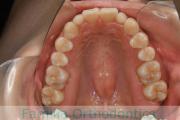

No.22V-409

- 叢生

- 年齢:

- 16歳

- 性別:

- 女性

- 抜歯部位

- 上:

- 44

- 下:

- 8|58

- 主な使用装置:

- FEA

- 治療にかかった費用:

- 86万円

八重歯を治したいということで来院されました。下あごの左ずれのある上顎前突(出っ歯)・叢生(でこぼこ)でしたので、上は左右から、下はで左のみ小臼歯を抜歯して、歯科矯正用アンカースクリューとマルチブラケット法にて治療を行いました。2年強、30回程度の通院が必要でした。

上下とも前歯の叢生(でこぼこ、凹凸、ガタガタ)があるため、保定を怠ると後戻りのリスクがあります。

- ≫治療前

-

上顎

下顎